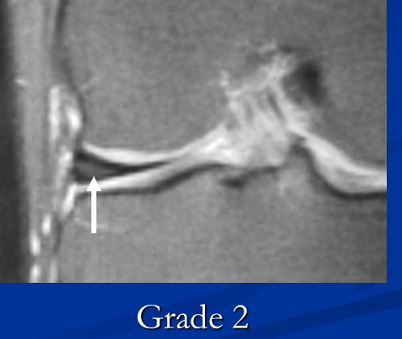

2级(II级):半月板内部出现线形的中等信号增高影,可延伸到半月板的关节囊缘,未达半月板表面。

(II级:半月板内部线行高信号,未达半月板的上或下表面)